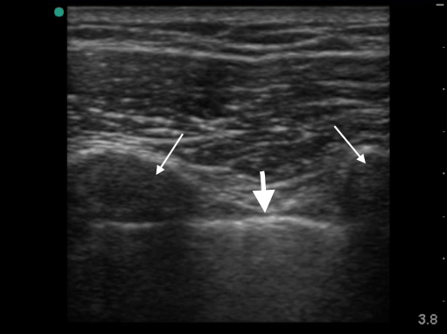

Lung Assessing Lung Collapse (Sonosite PX L12-3) Image

Pleura

Ribs